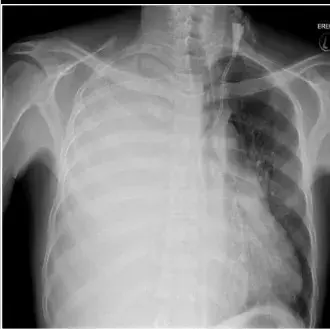

Uma causa incomum de hematúria glomerular intermitente!

Hematúria pós infecção, caso clínicos para auxiliar no entendimento de causas glomerulares comuns e raras...